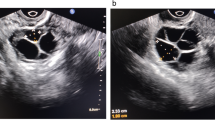

A total of 64 DOR patients, comprising 32 in the GH group and 32 in the control group, were included in this study. The clinical characteristics of the participants are presented in Table 1. The baseline characteristics were comparable between the GH and control groups, including age, BMI, duration of infertility, previous conception, previous IVF attempt, AMH, AFC, in addition to the levels of basal FSH, luteinizing hormone (LH) and estradiol (E2). There was no significant difference in the days of stimulation, FSH dose, or LH dose between both groups. It was noteworthy that the number of follicles above 14 mm on the day of hCG was significantly higher in the GH group compared to the control group (3 vs 2, p = 0.03; Fig. 1A). More importantly, this difference was also found for the number of oocytes retrieved between the GH and control groups (3 vs 2, p = 0.04; Fig. 1B). Moreover, there were trends toward higher E2 levels on the day of hCG (1380.8 ± 638.2 vs 1160.3 ± 582.6, p = 0.15) and normal fertilization rate (82.4% vs 69.1%, p = 0.05) in the GH group compared with the control group.